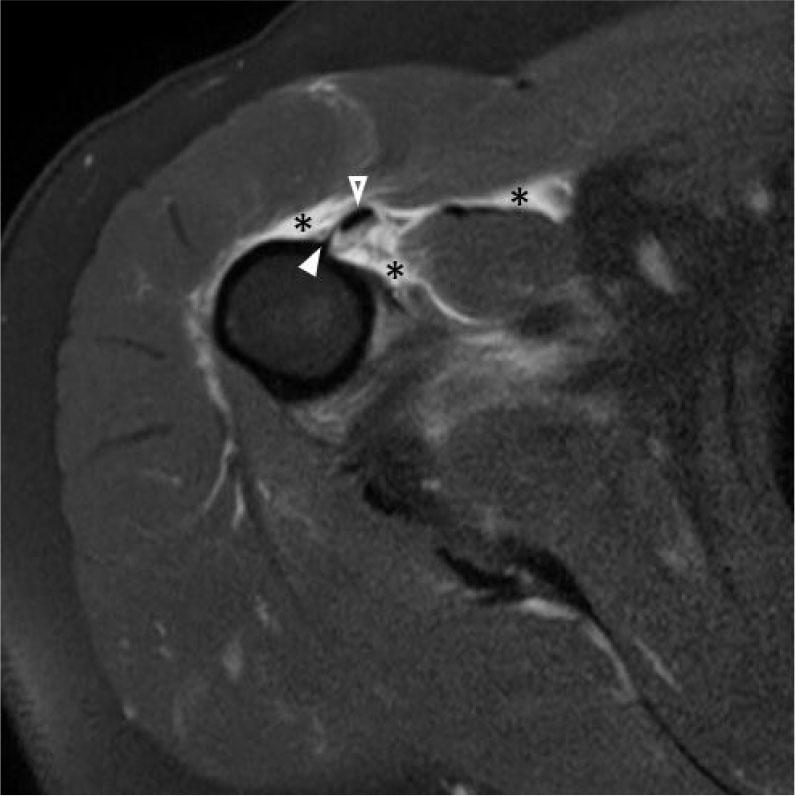

Fig. 13.

Axial T1 (A) and axial fluid-sensitive (B) MR images show focal fat at site of discontinuous muscle fibers (A, between arrowheads) from a chronic tear. Note the paucity of associated edema on the fluid-sensitive sequence (B, circle). C. Short axis gray scale ultrasound image shows a thickened and retracted torn PM tendon stump medially (between arrows). D. Corresponding MR image shows the retracted tendon stump (between arrows) with relative paucity of surrounding edema in this patient with chronic PM tear. Fibrosis was confirmed intraoperatively, which can also be seen with chronic tears